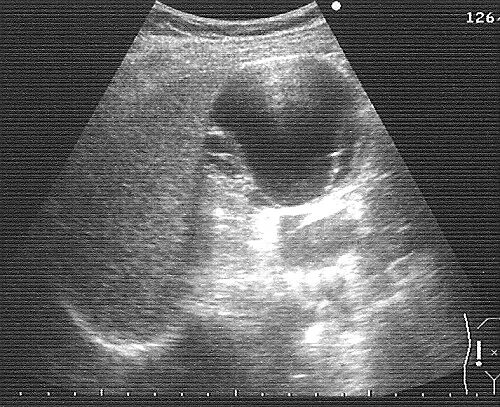

Можно вылечить кисту почки